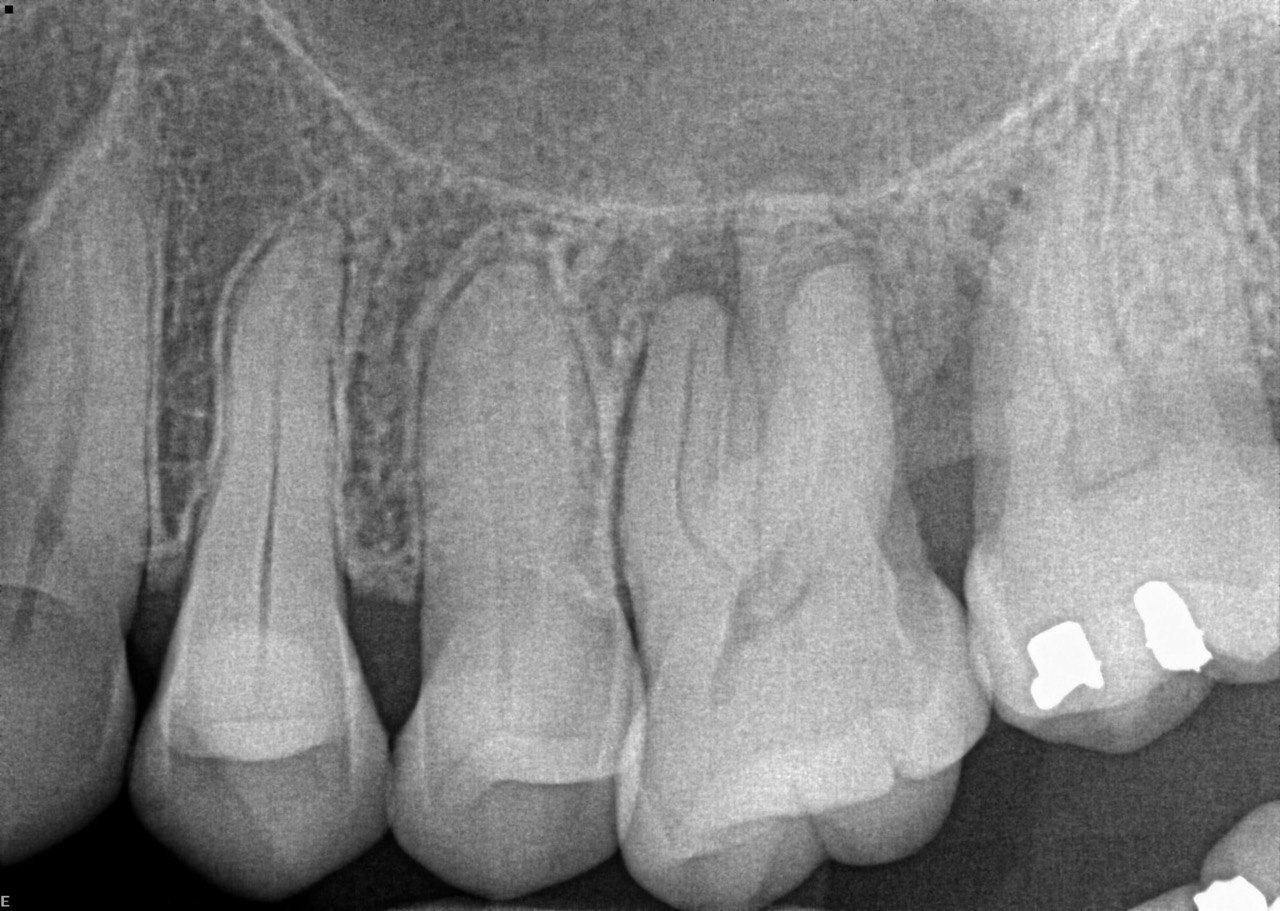

1. What is the condition in the distal surface of the tooth # 4.6?

2. What is the condition in the distal surface of the tooth # 4.7?

3. What condition can be detected in mesial surface of the tooth # 2.5?

4. What is the condition in the distal surface of the tooth # 3.4?